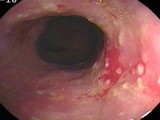

食管憩室

十二指肠球部溃疡

结肠癌

腺瘤

食管静脉曲张

食管炎

溃疡性结肠炎

锯齿状腺瘤

管状腺管腺瘤

小肠绒毛及淋巴滤胞

小肠绒毛

绒毛状腺瘤

肠息肉

直肠癌

增生性息肉